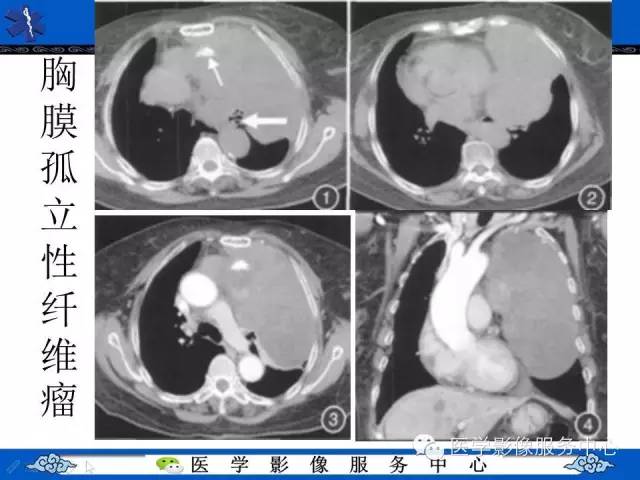

胸膜孤立性纤维瘤1例CT影像表现与鉴别

【病例】胸膜孤立性纤维瘤1例CT影像表现与鉴别